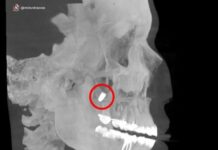

Причиной экстренной госпитализации стали интенсивные боли, которые женщина терпела три дня. Установленный двумя неделями ранее гастробаллон для сокращения объёма желудка спровоцировал прободение стенки органа. Это позволило содержимому желудка проникнуть в брюшную полость, вызвав опасное воспаление.

В ходе срочной операции врачи эндоскопически извлекли баллон через пищеводный канал. Благодаря профессионализму хирургов и современным методикам, критическая ситуация была быстро устранена. После периода восстановления в стационаре женщина выписана и продолжает амбулаторное лечение под постоянным медицинским контролем.